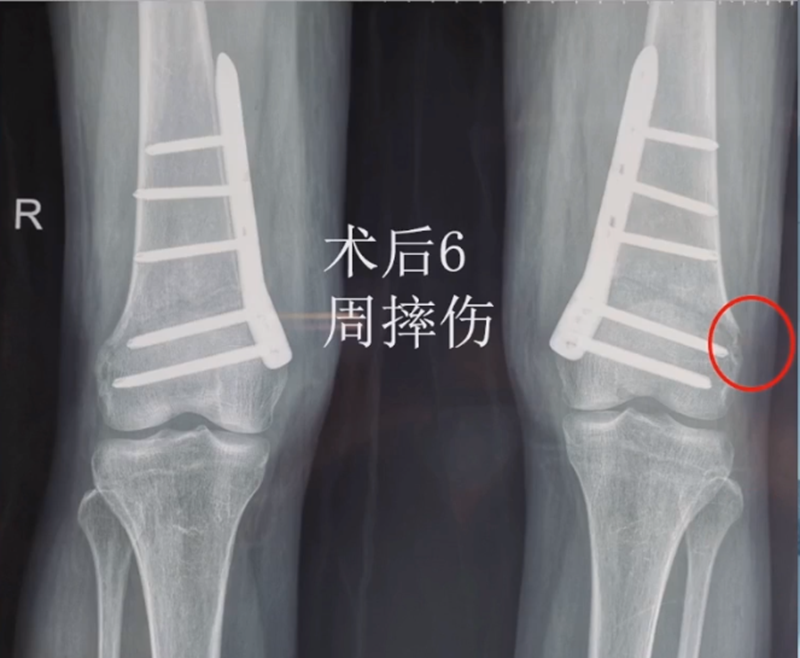

术后6周摔伤,一侧出现膝内翻。

影像学检查显示左侧出现合页断裂。

进行翻修,术前力线显示内翻。